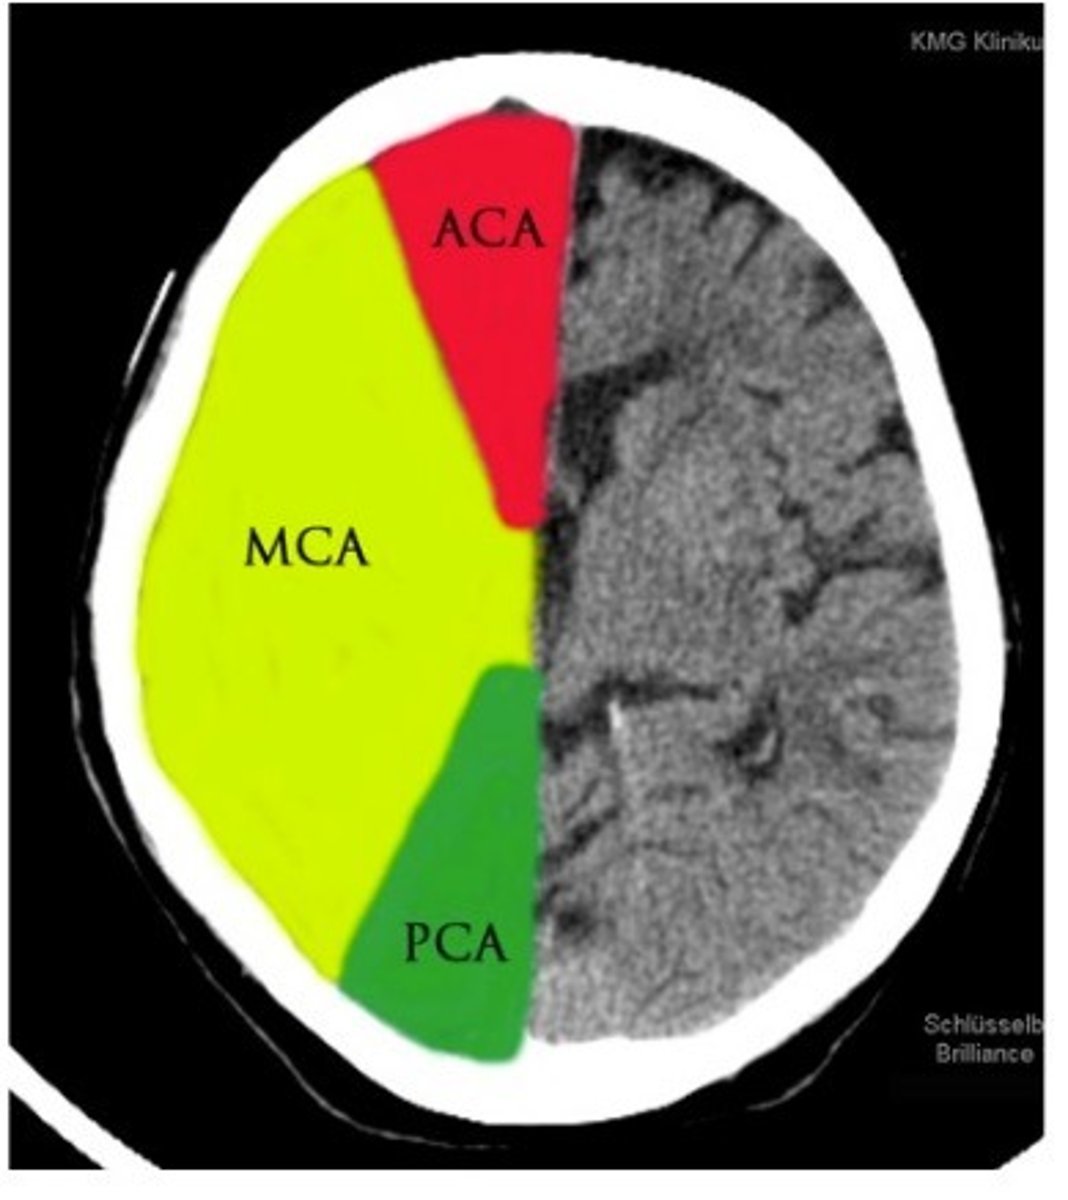

Anterior cerebral artery

medial surface, blood to foot and leg area of motor strip

middle cerebral artery

very common area for stroke

impacts brochas and werinkies area (depending on where stroke is)

outside of brain

posterior communicating artery

The artery that connects the basilar artery to the circle of willis. Supplies occipital lobe, branches off of posterior cerebral artery.

posterior cerebral Artery

supplies occipital lobe

Anterior Cerebral Artery (ACA) infraction

foot and leg dragging

Middle Cerebral Artery (MCA) infraction

broca's/wernikies aphasia

posterior cerebral artery (PCA) infraction

loss of sight and smell